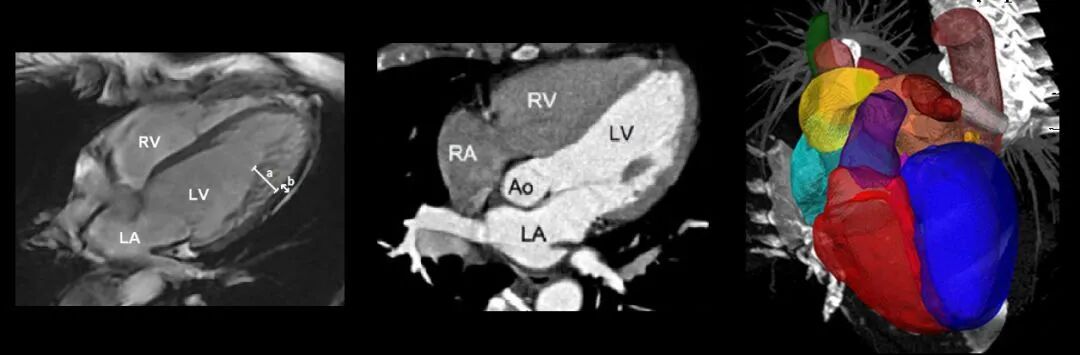

在心脏分割问题中,通常按结构将心脏分成几个标注区域。比如以MM-WHS数据库为例,有:

左心室血腔(the left ventricle blood cavity, LV)

左心室心肌(the myocardium of the left ventricle, Myo)

右心室血腔(the right ventricle blood cavity, RV)

左心房血腔(the left atrium blood cavity, LA)

右心房血腔(te right atrium blood cavity, RA)

升主动脉(the ascending aorta, AA)

肺动脉(the pulmonary artery, PA)

这些区域由于本身的特性,其难易程度和分割手段也存在不同。通常来讲,普适性的心脏分割算法能够实现基本的区域分割,但是要实现精准分割还是需要对单独区域进行单独处理。相对而言,右心室(RV)的分割难度更大,我们就以此为例分析一下其存在的难点。

2. 完整心脏分割

基于P3D和FPN实现完整的心脏分割:

Zhanwei X., Ziyi W., and Jianjiang F.. CFUN: Combining Faster R-CNN and U-net Network for Efficient Whole Heart Segmentation[C]. CVPR 2018.